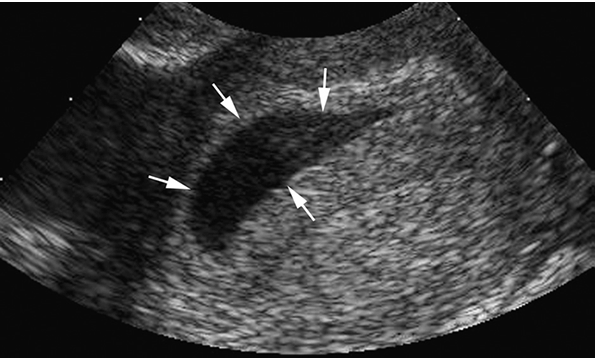

Type A: lớp dịch cho hình ảnh có đường viền tăng sáng, có phản âm bên trong lớp dịch. Thường gặp hình ảnh này nhất trên siêu âm trong những trường hợp thai ngoài tử cung (>70% trường hợp thai ngoài trong nghiên cứu này).

Vị trí của dịch lòng tử cung cũng được ghi nhận trong nghiên cứu này. 55% lớp dịch trong lòng tử cung ở những trường hợp thai ngoài nằm chính giữa lòng tử cung; 18% lớp dịch quan sát thấy ở lớp màng rụng và 27% lớp dịch nằm ở vị trí không rõ ràng trong lòng tử cung.